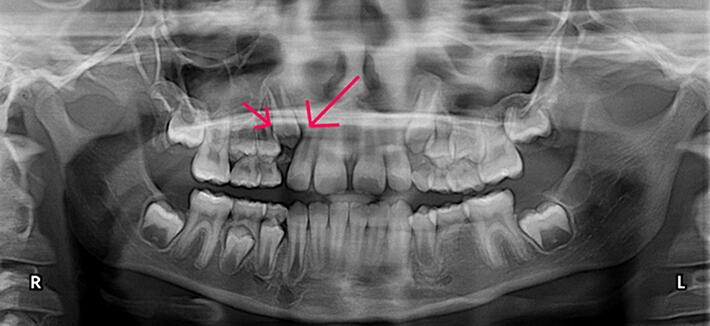

Early Loss Case

Patient presented with early loss of primary tooth #6 and impaction of adult tooth #6. During phase I treatment, space was created for tooth #6, and the tooth erupted without damaging neighboring teeth.